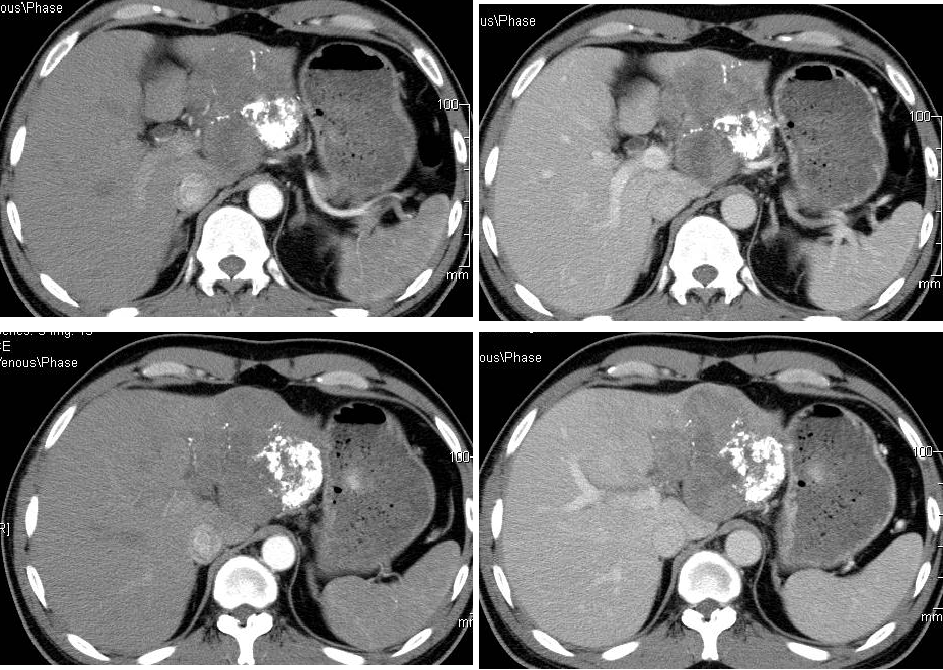

2011-08-15复查CT示:肝左叶病灶大小较前相仿,仍有肿瘤残留。

AFP:4095 ng/ml。

患者目前肿瘤大小与前一次复查相仿,未见继续缩小,影像学检查提示肝内肿瘤仍有活性;而且AFP仍然居高不下。

2011-08-22(第3次TACE后2个月) 行CT引导下微波消融+无水酒精固化术